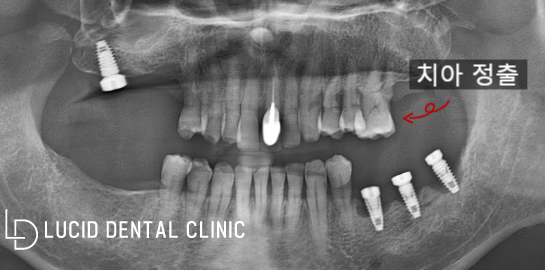

루시드 역삼동 치과 에서

초진 파노라마를 확인한 결과,

이미 타원에서 픽스처 식립만

받은 모습을 볼 수 있었는데요

타원에서 진행하던 도중, 내원을 미루게 되면서

자연스럽게 현재 상태로 생활하고 계셨다고 합니다.

게다가 말씀드린 대로 대합치 정출과

치조골 흡수 또한 나타나고 있었는데요